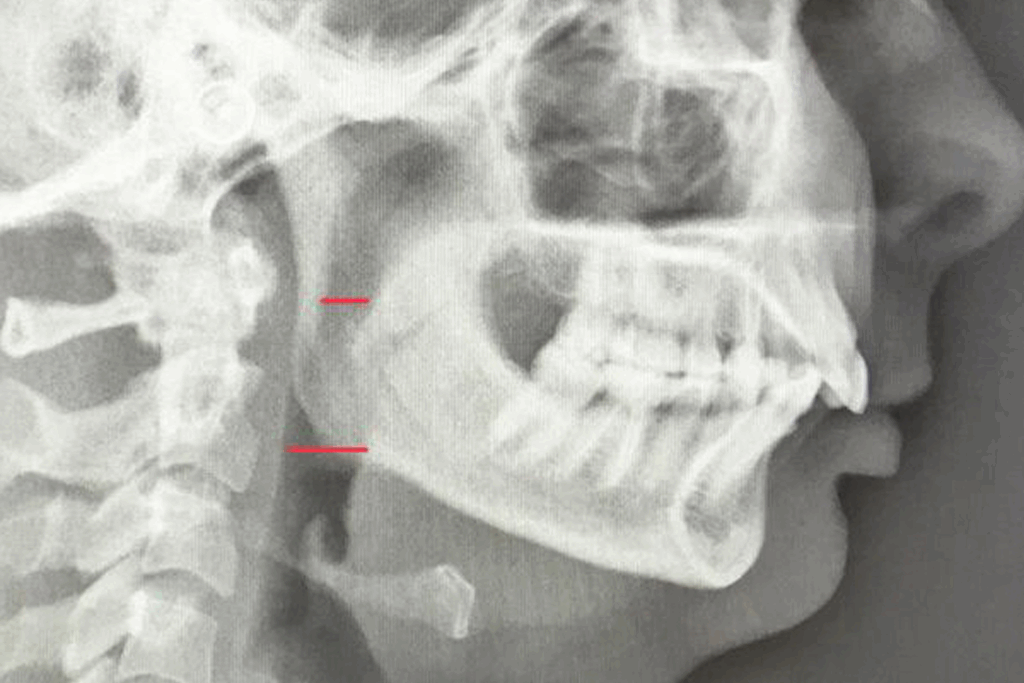

La gestion des classes II squelettiques